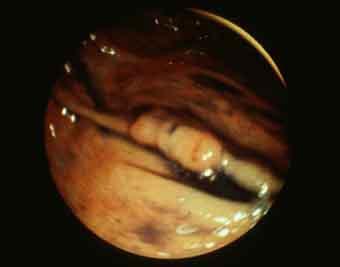

질환(병리주체)의 분류 악성 상피성종양/선암

부위(장기별) 대장/상행

검사방법 내시경

종양의 육안분류 0형(표재형)/IIa형(IIa)

종양의 최대경(밀리미터) 10~14

종양의 심달도 m